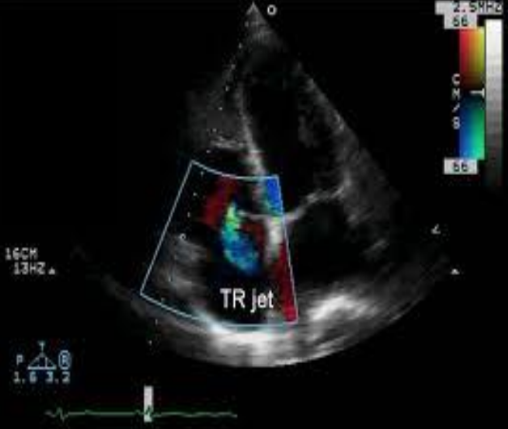

Colour Doppler is useful with TR by doing what?

Isolating where the TR jet is directed and is helpful with small eccentric TR jets.

The colour flow Doppler of a TR has what colour in diastole?

A blue jet demonstrated in the RA in systole.